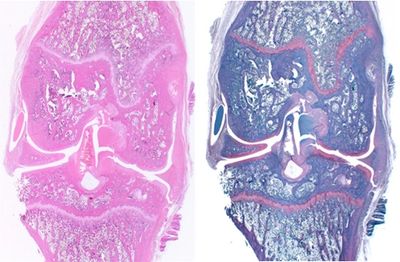

Osteoporosis is a skeletal disorder characterized by compromised bone strength and increased risk of fractures. The ovariectomy (OVX)-induced model is one of the most widely used and reliable animal models for postmenopausal osteoporosis. Removal of the ovaries mimics the hormonal changes that occur after menopause, leading to bone loss and skeletal fragility.

Histology markers:

Representative readouts: